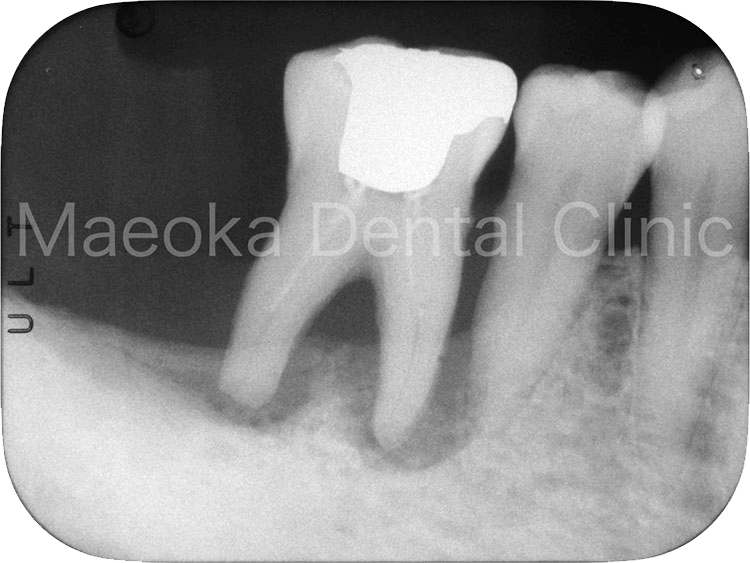

Case6

患者さんは78歳の男性の方で、「右下の奥歯がバキッといって痛みがあるので診て欲しい」という主訴で来院されました。

食事の際に痛みが走ったとのことでしたが、お口の中を確認すると生活歯(神経が抜かれていない歯)の右下6が半分に破折してしまっていました。

通常であれば抜歯が適応となるような状態の歯でしたが、患者さんに時間と費用がかかることに同意していただいた上で保存を試みることになりました。

頬の筋肉が発達した方だったので神経の治療を行うだけでも多くの時間を要し、治療開始から約9ヶ月後にメタルセラミックスの被せ物をセットして治療を終えました。

患者さんは「見た目は気にしないのでせっかく残してもらった歯が長持ちする被せ物にして欲しい」とおっしゃっていたため、咬合面(噛む面)は強い力がかかった際に変形することで力を逃しやすいメタルを選択しています。

治療と並行して歯が割れた原因にもなっていた咀嚼力のコントロールも実践していただいています。

治療終了から約5年が経過していますが、現在のところ目立ったトラブルは生じていません。

治療前(デンタル)

治療後5年経過(デンタル)